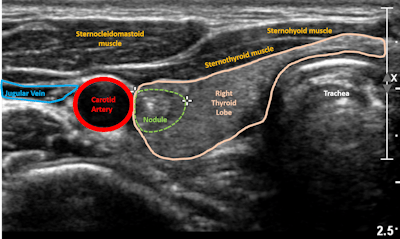

Ultrasound image of thyroid nodule. Image courtesy of Dr. Elizabeth Cottrill, Thomas Jefferson University.The team found that the algorithm's specificity was high -- an indicator of a low rate of false positives -- as was its positive predictive value (PPV). Its overall accuracy was 77.4%.